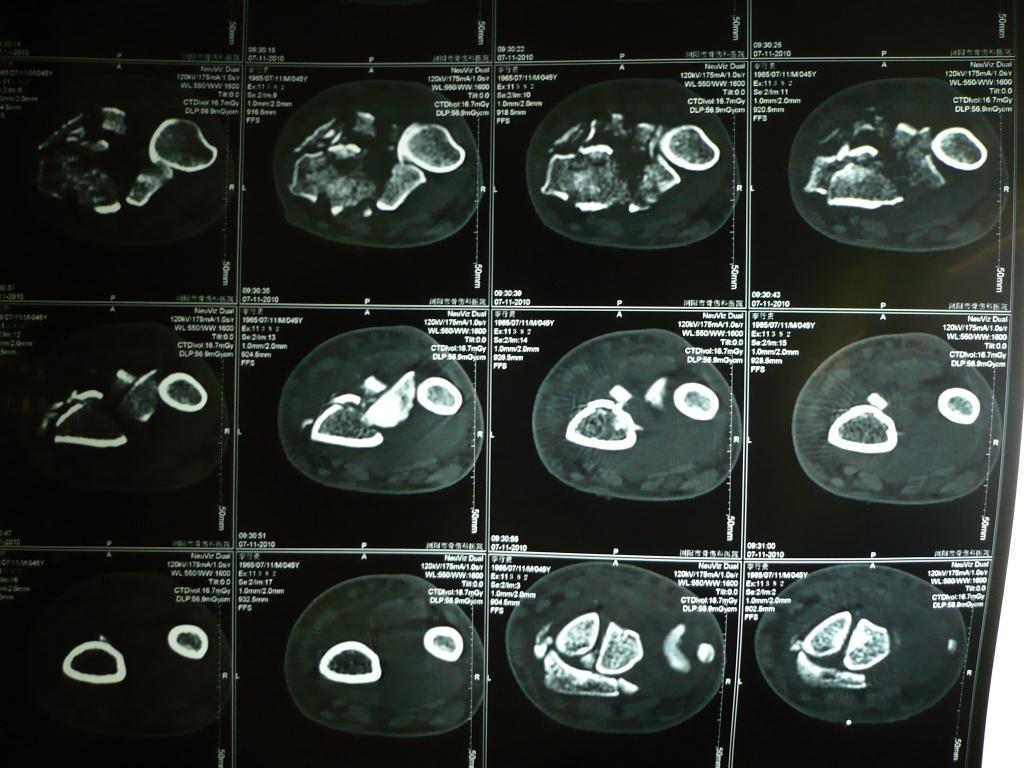

患者男性,45岁,外伤后6天,拟明天行开放复位内固定术。请战友指导手术方案及细节!

x片提示:右桡骨远端严重粉碎性骨折伴下尺桡关节脱位。建议:1.手法复位可能达不到想要的目的,关节面恢复不完整,创伤性关节炎不可避免。病员正是壮年,若是老年人,她对关节活动要求不高的话,也可以,(沟通清楚后)我们遇到很多老年患者,叫做手术,坚决不做,其要求不高。2.对于这个患者,建议手术治疗(手术目的:尽量恢复关节面的完整,恢复关节间隙),治疗方案有三:a掌背侧切开解剖复位,必要时植骨,细钢针固定,恢复关节面,缝合,外固定支架固定。 b,掌背侧切开解剖复位,必要时植骨,细钢针固定,恢复关节面,长的重建钢板自桡骨到第二掌骨固定。c术中看如果远端能曾受螺钉的话,也可以考虑“T”行钢板固定。